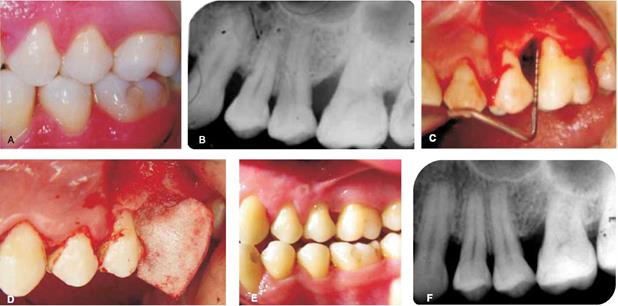

Se presenta a la Clínica de Periodoncia, paciente de sexo femenino de 33 años de edad, de escolaridad profesional, sin antecedentes personales patológicos de relevancia, la paciente es sistémicamente sana, no toma ningún medicamento, no fuma y no había recibido con anterioridad terapia periodontal. Se tomó serie radiográfica completa ( Figura 1 ). Durante el examen bucal se valoró porcentaje de los sitios gingivales que exhibían la presencia de placa bacteriana, sangrado al sondeo, profundidad al sondeo y recesión gingival.

En base a lo anterior, el diagnóstico periodontal fue: periodontitis agresiva generalizada ( Cuadro I).